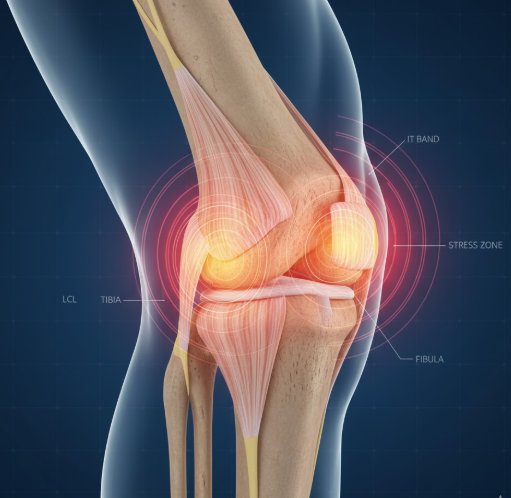

3) 무릎 바깥쪽 통증의 원인

- 장경인대 증후군

- 무릎 바깥쪽 통증의 가장 흔한 원인

- 허벅지 바깥쪽에서 무릎 바깥으로 이어지는 긴 인대가 무릎뼈와 마찰하면서 염증 발생

- 마라톤, 자전거 같은 반복적인 운동 시 흔하게 발생

- 달리기 중이나 후에 무릎 바깥쪽이 타는 듯한 통증 특징

- 외측 측부인대 손상

- 무릎이 안쪽으로 꺾일 때 바깥쪽 인대 손상으로 발생

- 내측 인대 손상보다는 덜 흔함

- 접촉 스포츠나 교통사고 등에서 발생 가능